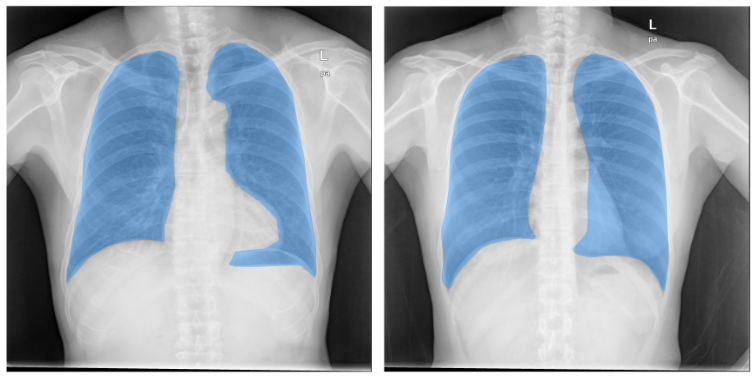

Table 2 shows the DSC of the predictions for ViT-H, the largest SAM model, with results for ViT-B and ViT-L shown in the Supplementary Material. The terms 1st, 2nd, and 3rd correspond to the three predictions generated by SAM, and the table presents the metrics when only one of these predictions is used consistently for all images. Fig 3 showcases an example of these predictions for the Chest X-Ray (CXR) dataset, employing both the RP5 and BBS10 strategies. The RP5 method provides better differentiation between predictions, while the BBS10 approach demonstrates greater uniformity. This observation could potentially be attributed to the bounding box, which simultaneously indicates the target region for segmentation and the areas to be excluded (outside the box).

Refer to caption

Figure 3: Three returning predictions from SAM using RP5 (A, B, C) and BBS10 (D, E, F) input methods for the CXR dataset. A physician may choose the one that best fits the corresponding region to be segmented.

4.2 Qualitative Analysis

The analysis of medical images presents a unique set of challenges due to the complex and diverse nature of datasets. For instance, the CXR dataset, which consists of chest X-rays and their corresponding segmentation masks, contains inconsistencies in the segmented regions, as depicted in Fig 5. Some ground-truth masks include the heart while others exclude it. Still, SAM can rapidly rectify these discrepancies by allowing users to select the most appropriate prediction, as demonstrated in Fig 3, or by refining input points to include or exclude specific regions as needed.

Figure 5: Example of inconsistencies within the ground-truth region in the CXR dataset.